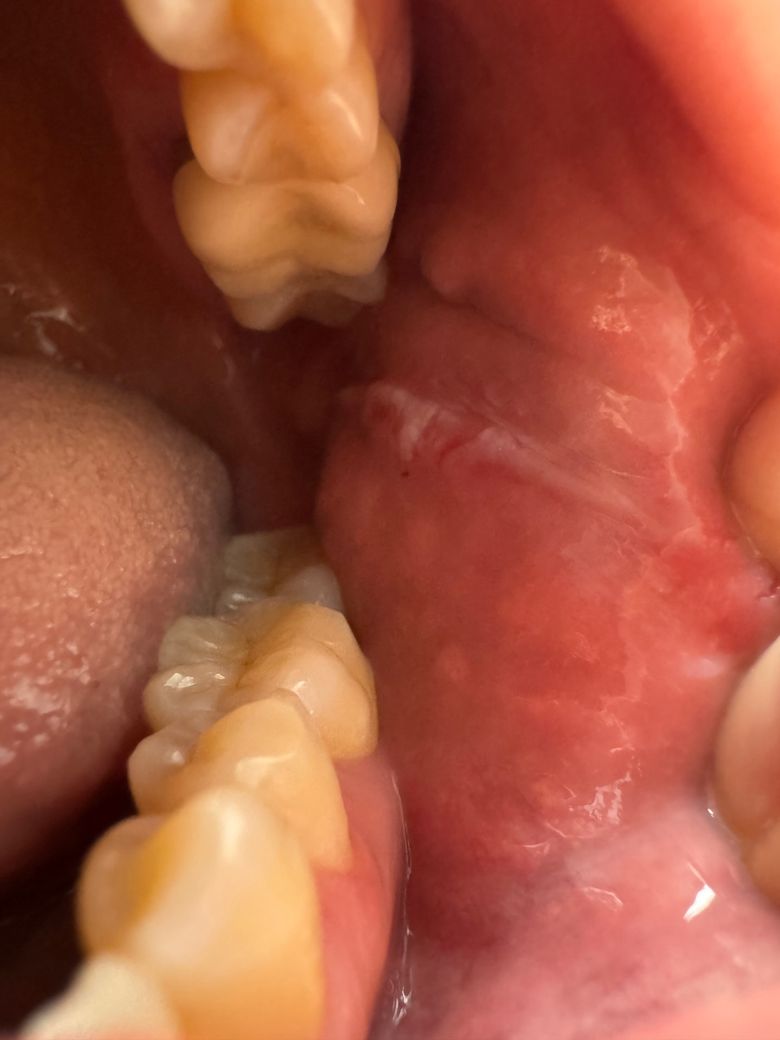

이게 뭘까요..?사진첨부합니다..

통증은 없는데 하얀줄이 생기고

중간은 벗겨진 것 같아요

사진으로 보이는 부분은 압흔으로 보입니다.

압흔은 치아에 너무 강한 힘이 작용하게 되어 연조족이 치아 사이에 밀려나면서 생기는 증상입니다.

아래 위 치아가 맞물렸을 때 생기는 일종의 선이라고 보시면 됩니다. 즉 치아가 맞물렸을 때 볼살이 안쪽으로 밀려 들어가면서 지속적으로 볼살을 자극하여 해당 선이 자주 생기게 됩니다. 이는 씹는 힘이 강할수록 자주 나타나게 되며 이갈이나 이를 악무는 습관이 있는 분들에게도 훨씬 선명하게 나타납니다.

사진에 보이는건 볼살이 치아에 씹히면서 생긴 볼의 표피입니다. 큰 문제가 잇는건 아니니 너무 걱정하지마세요.

사진상으로는 볼살이 씹힌 자국일 가능성이 높아보이며 자극이 가해지지않으면 괜찮아질겁니다.

무증상의 구강편평태선의 가능성이 있어보입니다 구강내과가서 정확히 진단받아보시기 바랍니다